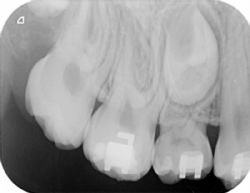

Einzelzahnaufnahme

Manchmal ist für Detailinformationen zusätzlich das Bild eines Einzelzahnes erforderlich (genaue Lagebestimmung verlagerter Zähne, Kariesdiagnose etc.)